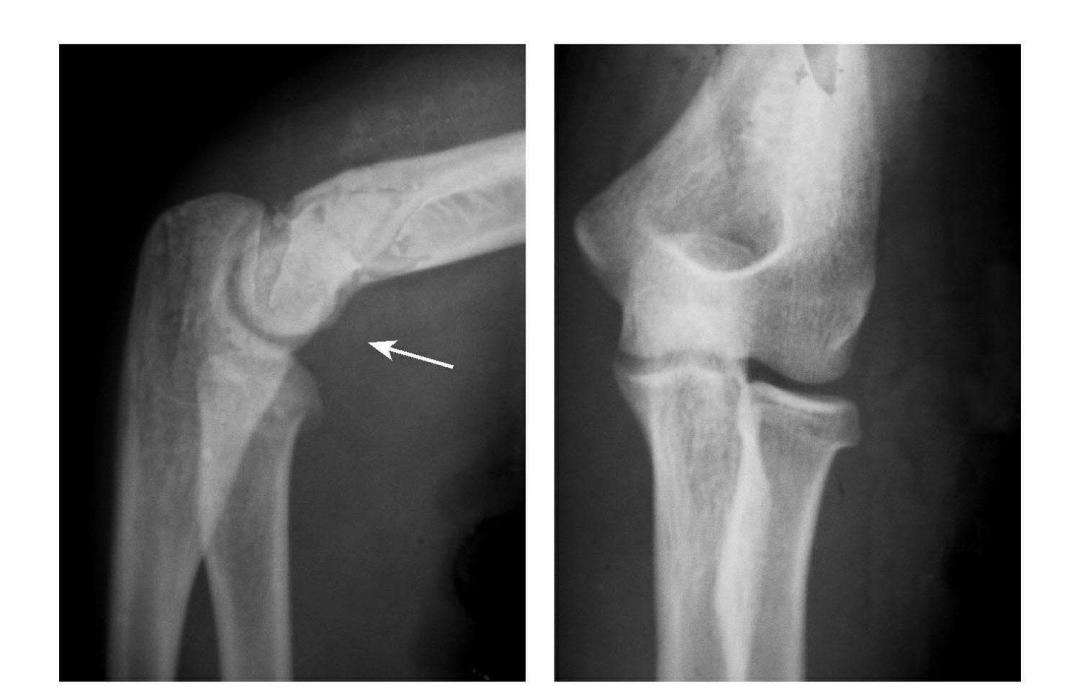

例1:肱骨小头软骨面及其下方少量骨质呈“新月样”被剥脱,且向肘前上方移位并桡骨头前半部骨折。

例2:肱骨小头软骨面剥脱性骨折,致该小头新月状骨片被向前脱位的桡骨头顶向肘关节前上方,并尺骨干中段骨折(孟氏伸展型骨折)。